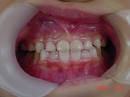

治療前 治療後

今回の症例は上下の前歯の位置関係が改善していますが、

顎骨の劣成長等の関係で

全ての症例で必ずしも前歯の位置関係が良好な状態となる訳ではありません。

また今後、2次・3次的な治療が必要となる可能性があります。